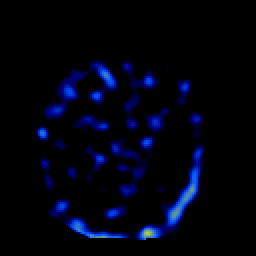

SPECT TL Study #2 -- Slice #24

[Home][Help][Clinical][Tour 1][Tour 2][Tour 3] Slice 24